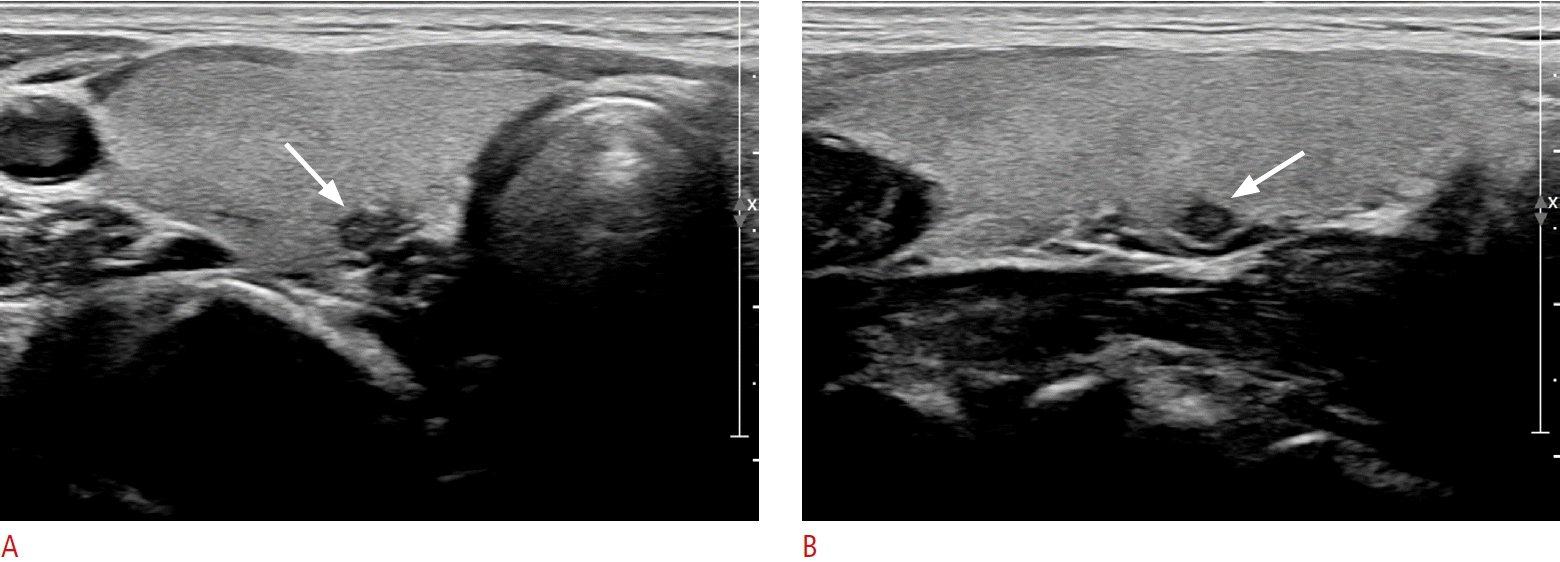

Examples of a subcentimeter fine-needle aspiration (FNA) not-indicated nodule according to Korean Thyroid Imaging Reporting and Data System (K-TIRADS).

Ultrasonography (US) from a 35-year-old woman shows a solid hypoechoic nodule without any suspicious US features. The nodule was classified as K-TIRADS 4, and as the size of the nodule was 3 mm. FNA was conducted in response to the patient’s request, and identified atypia with undetermined significance (A, transverse scan, B, longitudinal scan). Arrows indicate the aspirated nodule.